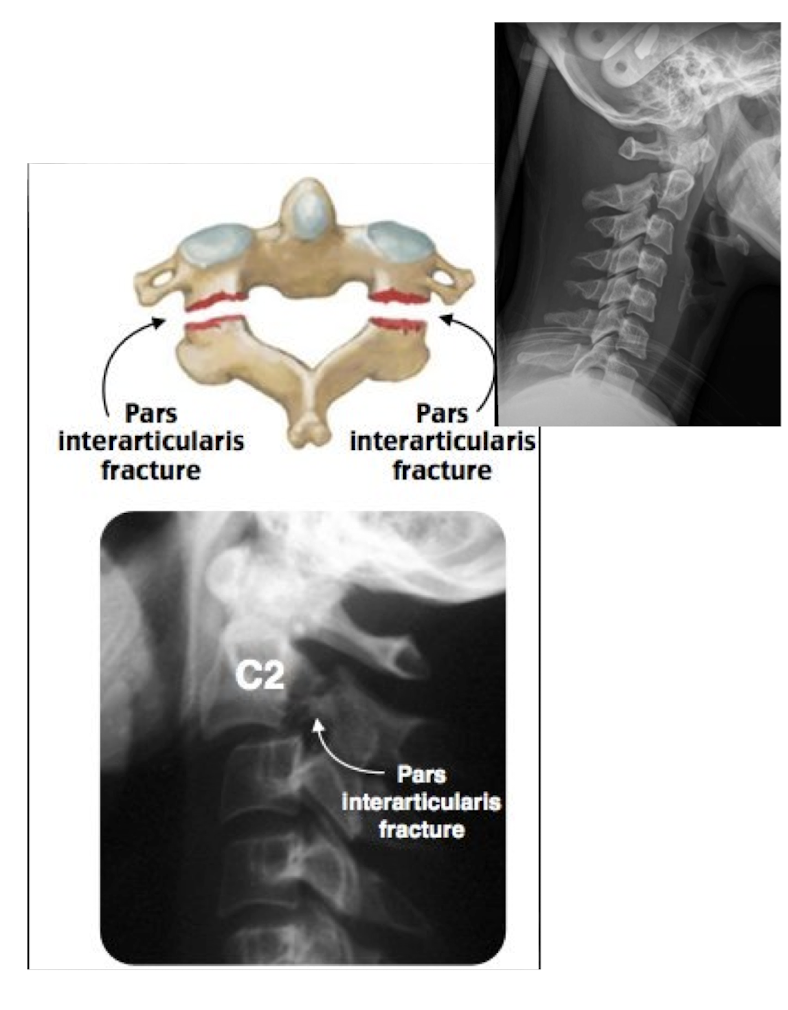

Fracture of C2: Hangman’s Fx

What type of Fx is this?

Bilateral Fx of the pedicles of C2 w dislocation of vertebral body C2 on C3

Fracture of C2: Hangman’s Fx

MOI:

__ for info on the SC

Stable or Unstable Fx

MOI:

Hyper Extension Injury in MVA

MRI

Unstable